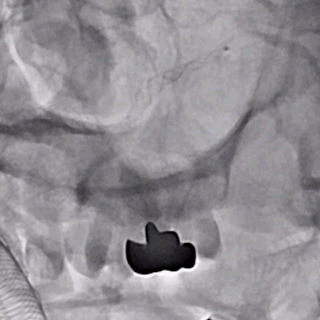

支架及支架微导管到位。

支架头端打开。

支架远端打开造影。

等张释放,支架中段打开至50%释放标记点。

支架中段打开造影。

支架近端打开,完全释放。

支架完全释放造影。

术后即刻造影。